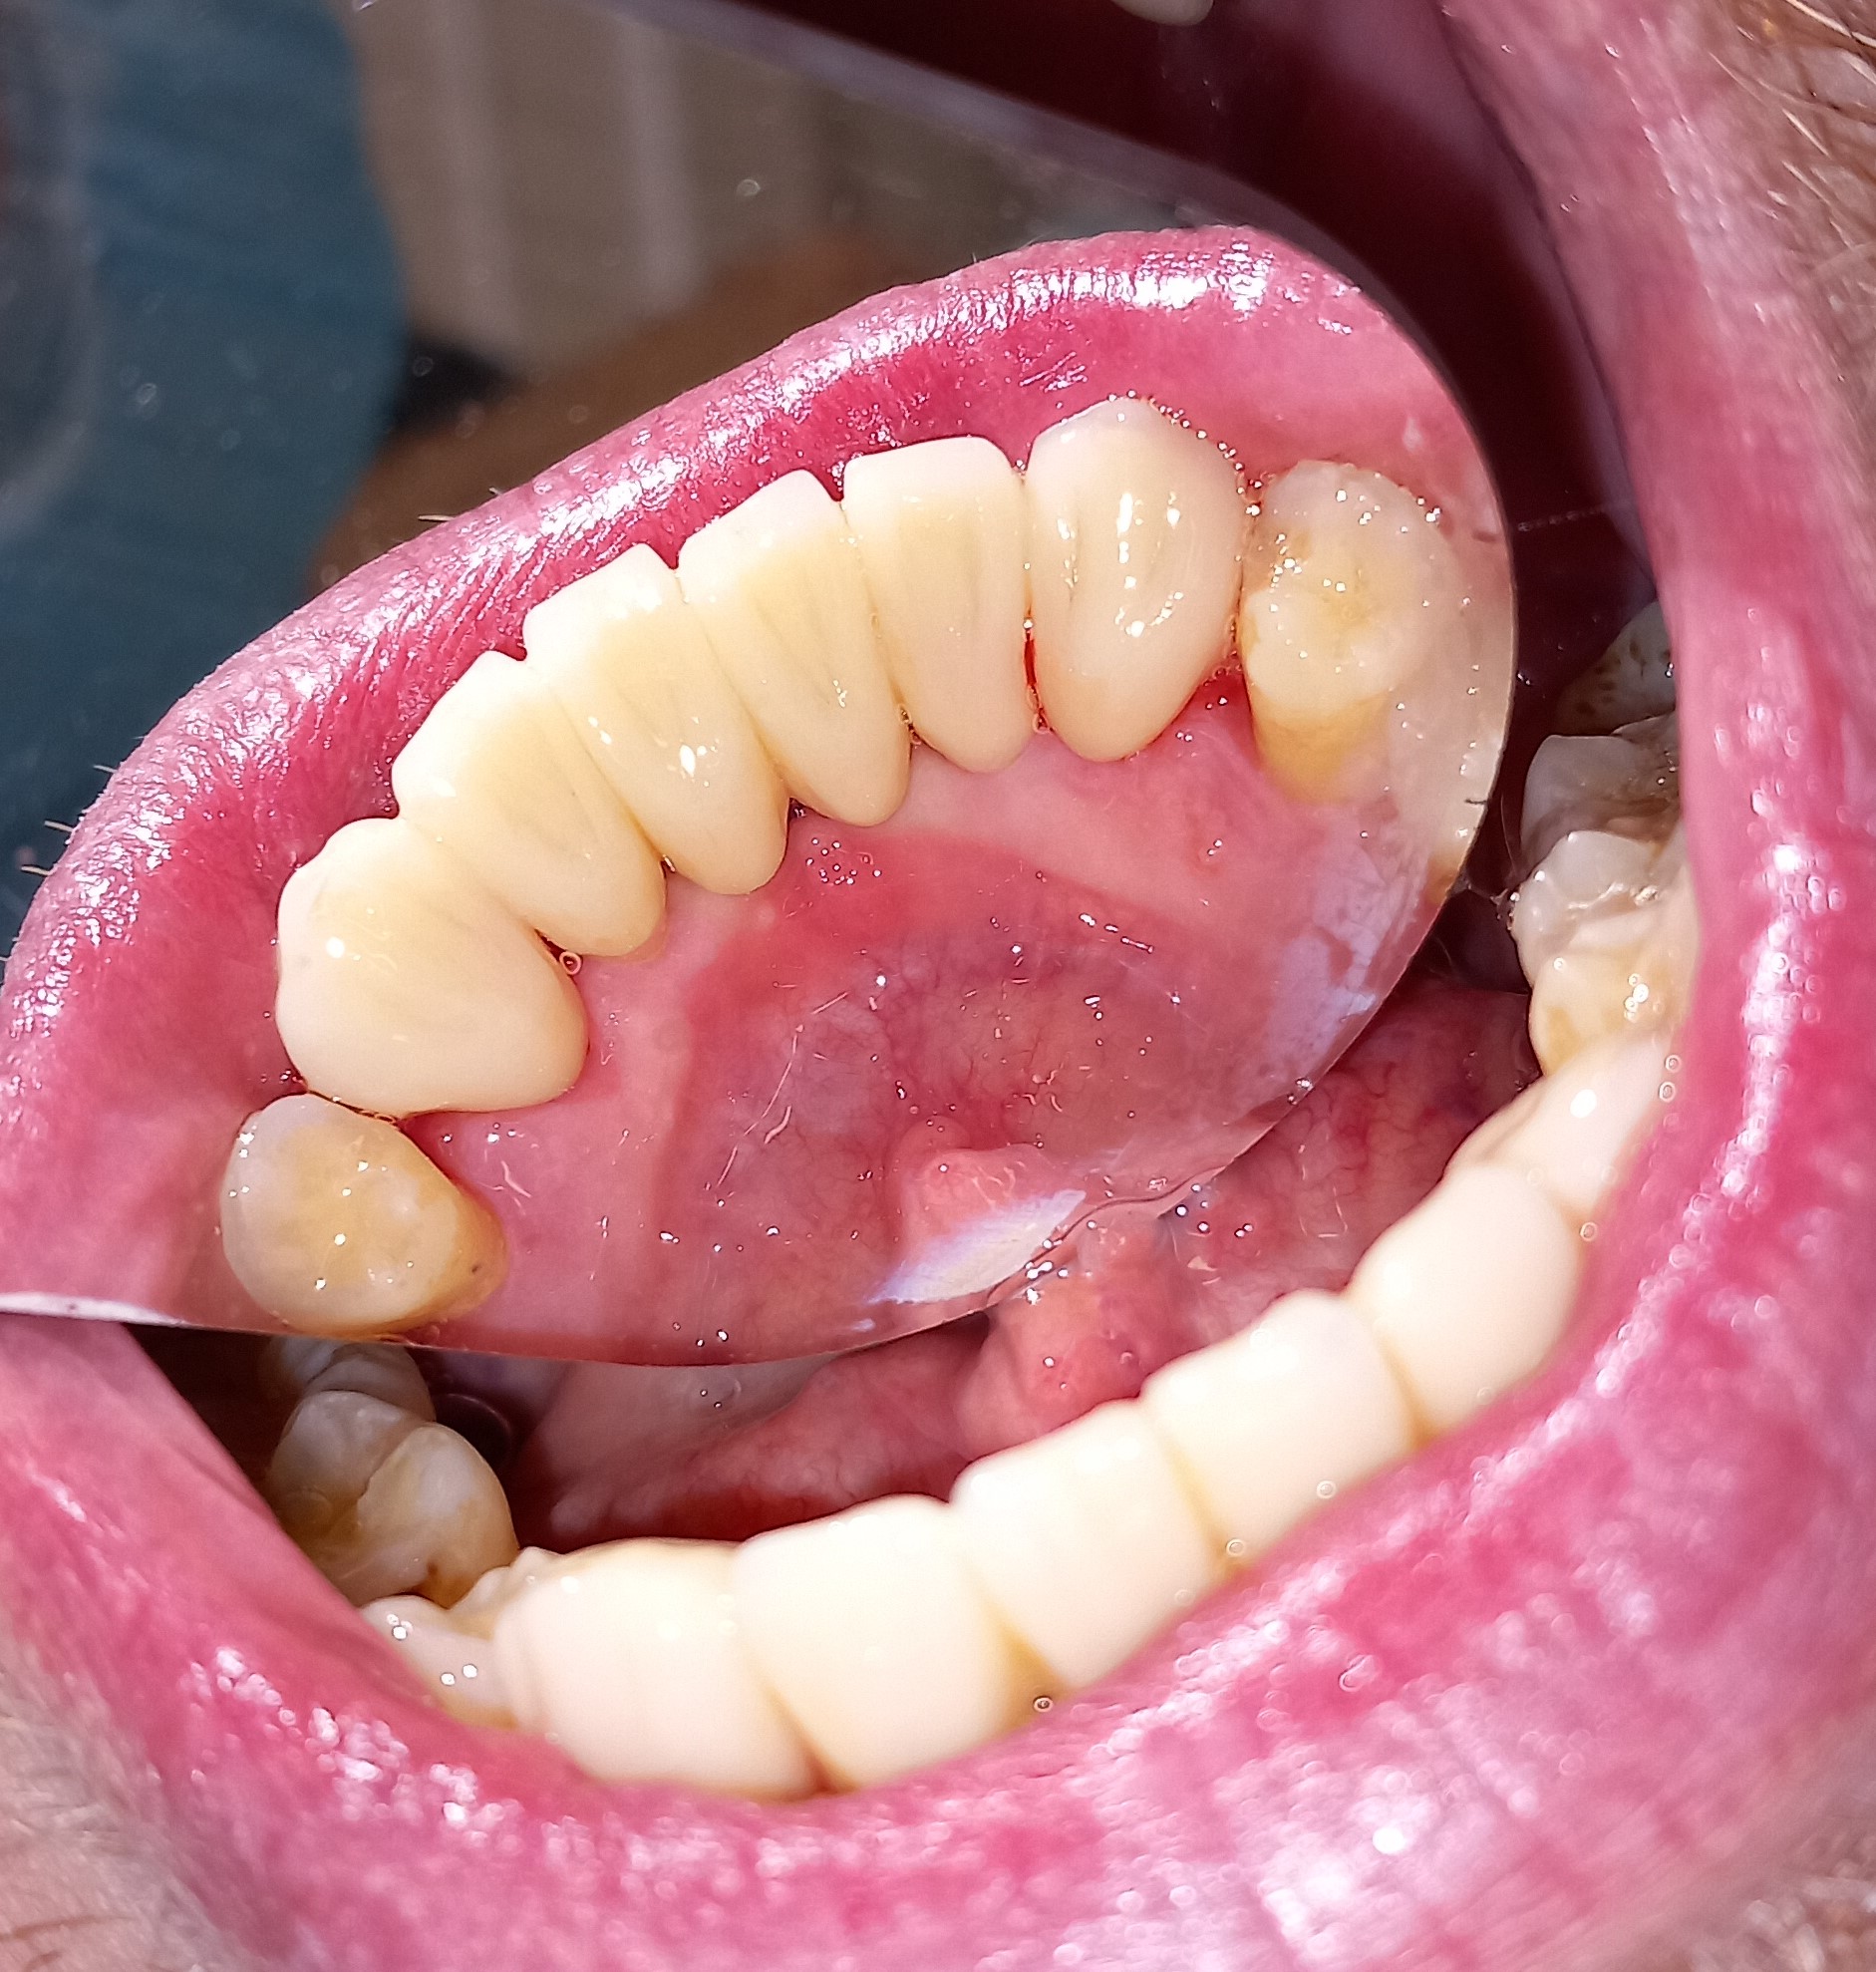

Ο ασθενής είχε πάρα πολλά χρόνια να επισκεφτεί τον οδοντίατρο. Πρόκειται για ένα απαιτητικό περιστατικό, κατά το οποίο ο ασθενής ήταν πολύ συνεργάσιμος καθώς ήθελε να αποκτήσει ένα όμορφο και λαμπερό χαμόγελο. Αρχικά εξάχθηκαν όσα δόντια δεν μπορούσαν να διατηρηθούν πλέον στο στόμα του ασθενή. Στη συνέχεια απονευρώθηκαν τα περισσότερα δόντια και ακολούθησαν ανασυστάσεις όλων των δοντιών. Εφόσον είχε αποκατασταθεί η φλεγμονή των ούλων λήφθηκαν αποτυπώματα και στάλθηκαν στον οδοντοτεχνίτη ο οποίος κατασκεύασε ολοκεραμικές θήκες, οι οποίες ήταν ενωμένες μεταξύ τους (ολοκεραμικό πέταλλο). Ο ασθενής φορούσε προσωρινή γέφυρα στο μεσοδιάστημα που χρειάστηκε ο οδοντοτεχνίτης να κατασκευάσει τη μόνιμη προσθετική εργασία.

ΠΡΙΝ

Ενδιάμεση κατάσταση αφού ολοκληρώθηκαν οι ανασυστάσεις δοντιών